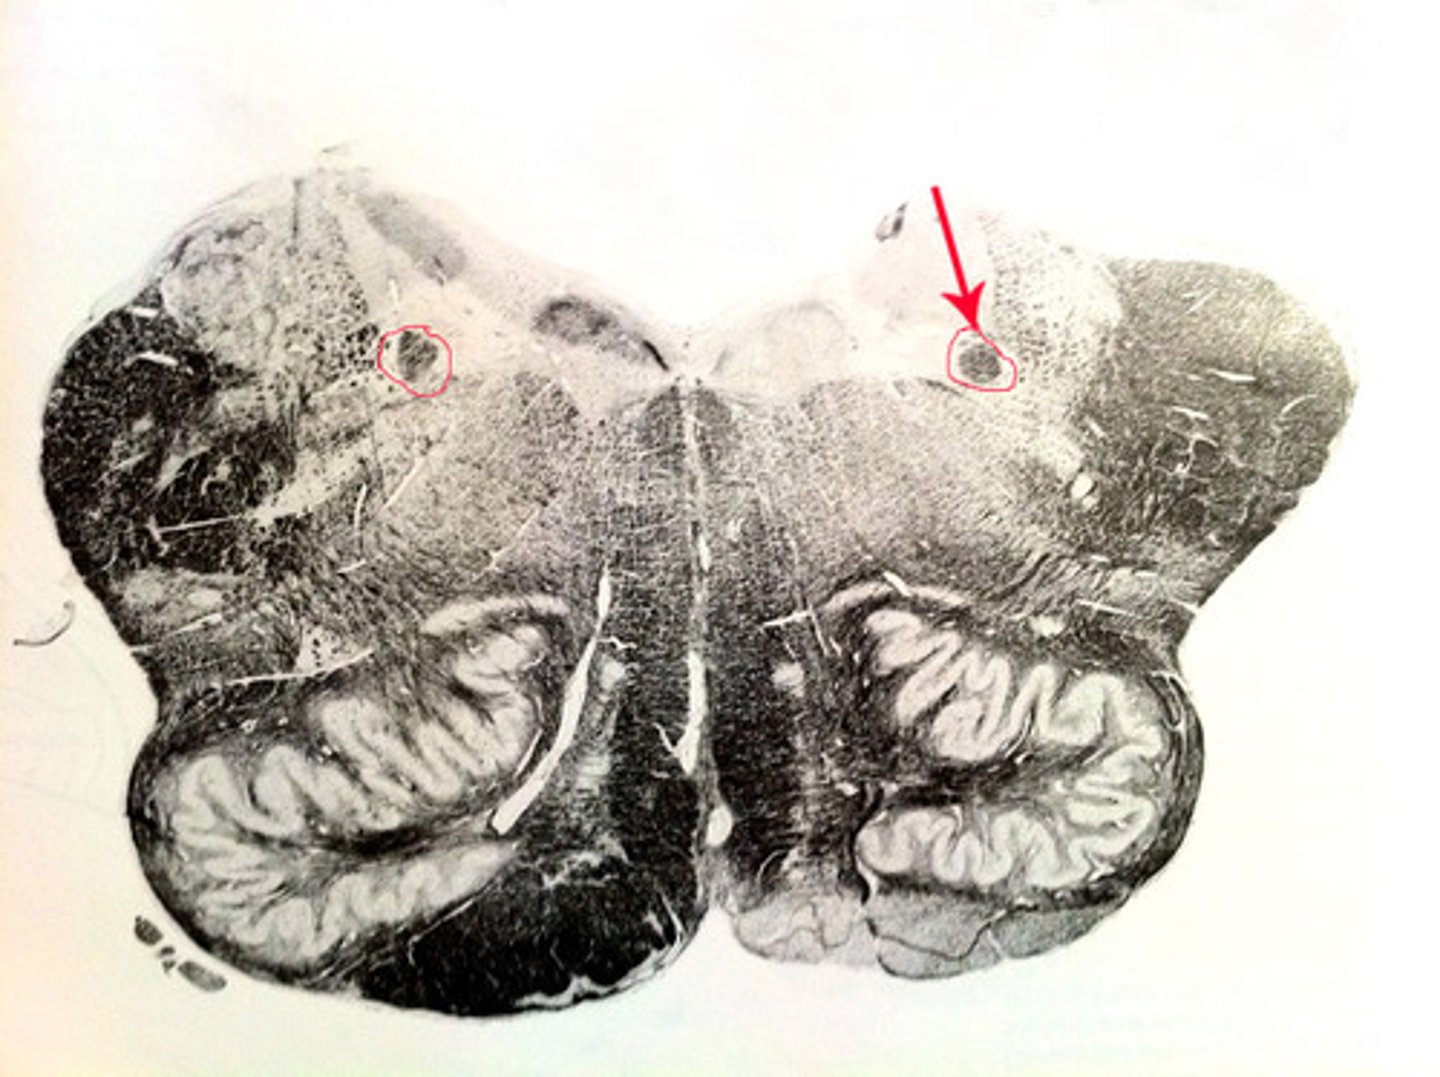

pons

center structure of the brain stem, located between the midbrain and the medulla oblongata

pontine nuclei

serves as relay striations between cerebral cortex & cerebellum in regards to motor coordination